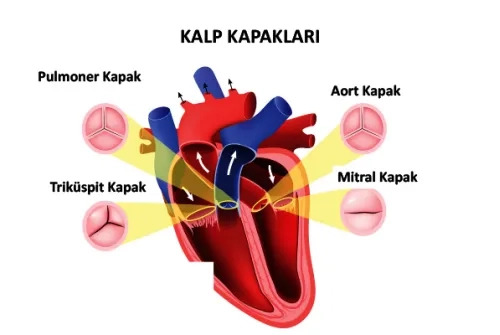

Kalp Kapak Hastalıkları Nedir?Kalp kapakçıkları, kanın doğru yönlere akmasını sağlayan organlardır. Bu kapakların düzgün çalışmaması, kanın geri kaçmasına veya yetersiz akışa n

Neden Kalp Kapakçığı Değişimi Gereklidir?Kalp kapakçıkları, kalbin kan pompalama işlevini yerine getirmesinde önemli bir rol oynar. Kapakçıklar hasar gördüğünde, kanın geri kaç